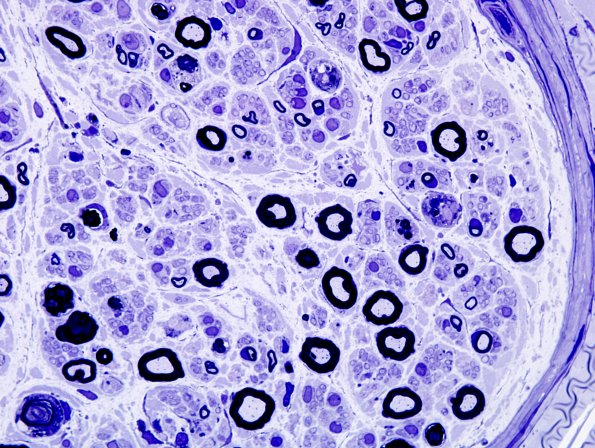

Washington University Experience | PERIPHERAL NEUROPATHY | 17 TOXIC NEUROPATHIES | Disulfiram | 1A5 Disulfiram (Case 1) Plastic 10

Along with a background of axonal degeneration and loss, there are scattered demyelinated axons in most fascicles. (plastic section)